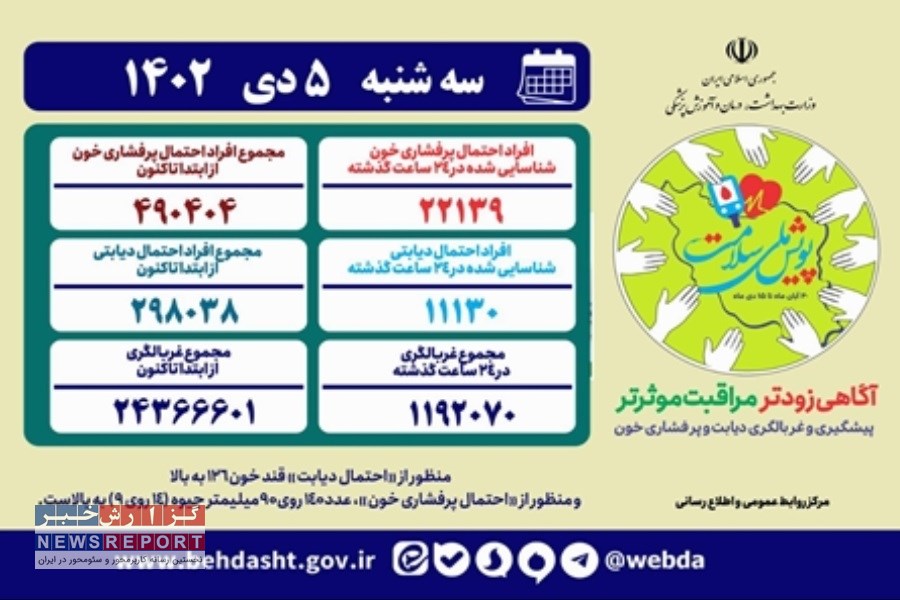

به گزارش خبرنگاران گروه جامعه گزارش خبر، از این تعداد ۵۱۳ هزار و ۵۵۶ نفر با احتمال ابتلا به پرفشاری خون و ۳۱۰ هزار و ۲۵۶ نفر با احتمال دیابت شناسایی شدند.

همچنین در ۲۴ ساعت گذشته یک میلیون و ۲۶۶ هزار و ۲۱۶ نفر در این پویش غربالگری شدند که از این تعداد ۲۳ هزار و ۱۵۲ نفر با احتمال پرفشاری خون و ۱۲ هزار و ۲۱۸ نفر با احتمال دیابت شناسایی شدند.

منظور از «احتمال دیابت» قند خون ۱۲۶ به بالا و منظور از «احتمال پرفشاری خون»، عدد ۱۴۰ روی ۹۰ میلیمتر جیوه (۱۴ روی ۹) به بالاست.